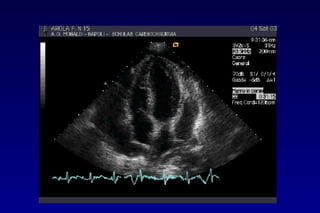

METODOLOGIA DI STUDIO

Uno studio completo del pericardio richiede

diversi approcci: parasternale asse lungo e

asse corto, apicale, sottocostale.

Uno studio completo del pericardio richiede diversi

approcci: parasternale asse lungo e asse corto,

apicale, sottocostale.

METODOLOGIA DI STUDIO VALUTAZIONE

SEMIQUANTITATIVA

• Lo spazio eco-privo solo sistolico tra i due foglietti

NON è considerato patologico

• Separazione sisto-diastolica: VP lieve, corrispondente

a 15-35cc.; se il versamento è circonferenziale: circa

300 cc.

• Se spazio eco-privo diastolico posteriore >10 mm: VP

> 500 cc.

• Se spazio eco-privo diast. post. >20mm: VP >700cc

 swinging heart (pseudo PM, movim. paradosso

siv)

>2cm

1.5 cm

<1cm

Versamento di lieve entità

(15-35 cc  300 cc)

Versamento di entità

Moderata (300-700 cc)

Versamento di

entità severa

(>700 cc)

Spessore max del versamento in diastole